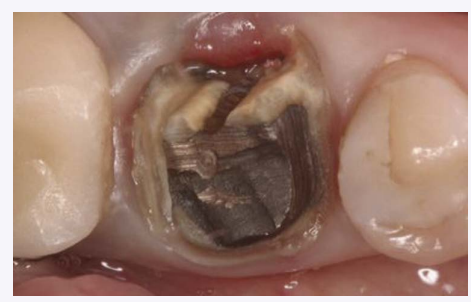

Clinical view of mandibular right first molar after PFM crown removal.

A 39-year-old woman presented with a failing mandibular right first molar under a fixed PFM prosthesis. The patient was in good health and had no medical contra-indications that would prevent routine dento-alveolar surgery. Pre-operative photographs and periapical radiographs were taken of the site. After bridge removal, the tooth was deemed hopeless. It was sectioned and extracted in an atraumatic manner using periotomes and luxators (Figs. 1-3).